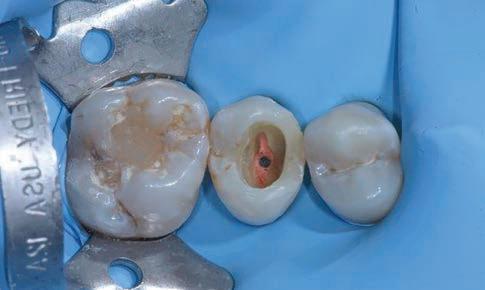

The canal was sealed with a Thermafil™ cone (Dentsply Sirona) with an apical diameter of 0.30 mm (Figs. 3-4).

Figure 3: Root canal therapy completed under proper isolation. Figure 4: Radiography of completed root canal therapy and reconstruction made completely in glass hybrid cement.